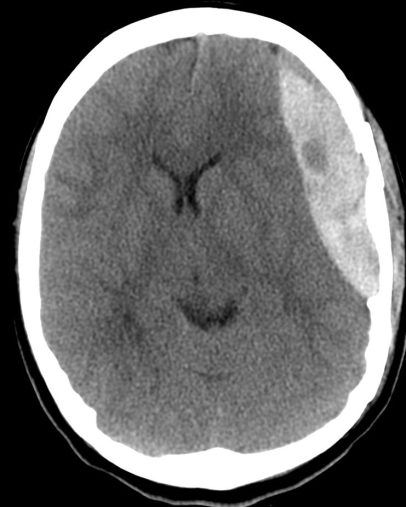

- Lente biconvexa hiperdensa. Si hay foco hipodensos en su interior puede indicar sangrado activo = signo del remolino = actitud quirúrgica.

- Normalmente limitada por suturas. Pueden cruzar la hoz y el tentorio

- Se localiza entre la duramadre y la tabla interna del cráneo.

- Suele ocurrir en el sitio de impacto por golpe directo que produce desgarro de vasos meníngeos arteriales y venosos.

- La arteria meníngea media es la más afectada y causa el hematoma temporo parietal.

- Se puede asociar con HSD por contragolpe, contusiones intracraneales y efecto masa.